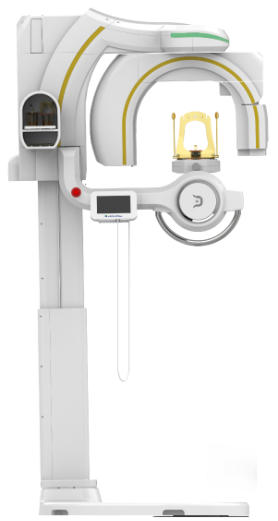

![]() PANO with Autofocus

PANO with Autofocus

2D panoramic feature with Autofocus for minimized distortion